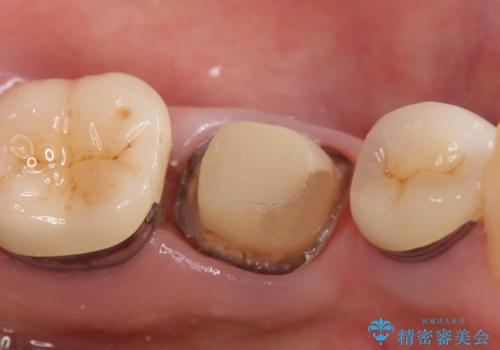

- 左下の奥歯でものを咬むと痛むので診て欲しいといらっしゃった方の症例です。

検査の結果左下6に根尖病変を認めたため、再根管治療を行いました。

その後症状の消失を確認し、オールセラミッククラウンによる補綴を行いました。